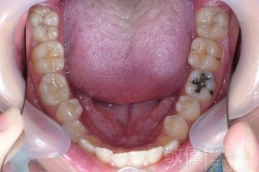

齒顏矯正/上顎暴牙且牙齒極度混亂

矯正前-上   矯正前-下

矯正後-上   矯正後-下

<個案說明>

上顎暴牙且牙齒極度混亂,經由矯正之後,臉型大幅度改善,牙齒的排列更加的整齊健康。相較於之前眼神充滿精神,自信心展現無遺。